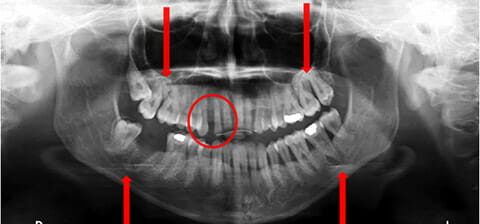

Panoramica prima e dopo la terapia parodontale, ortodontica ed estetica